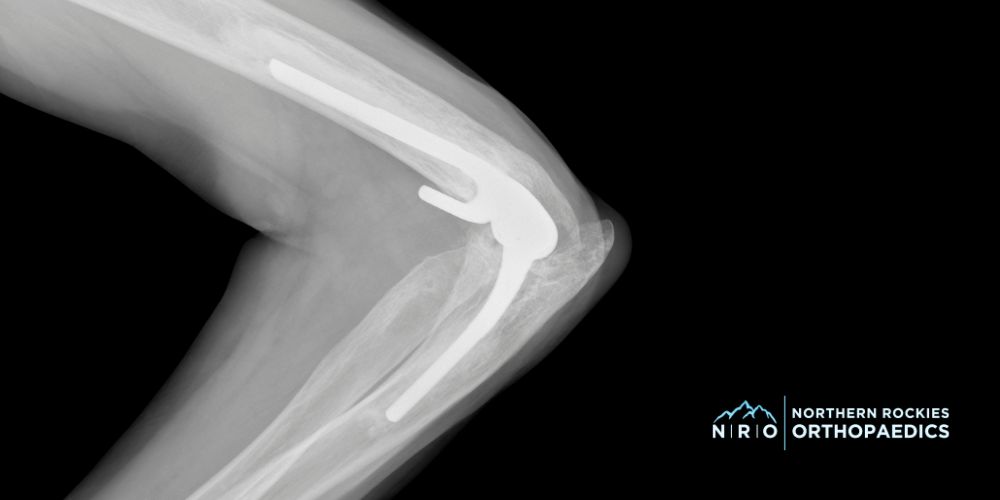

- Joint Replacement: Surgeons perform joint replacement in severe cases of rheumatoid arthritis, osteoarthritis, or complex fractures when the joint tissues are too damaged. They replace the damaged parts of the elbow with artificial components to restore movement and reduce pain.